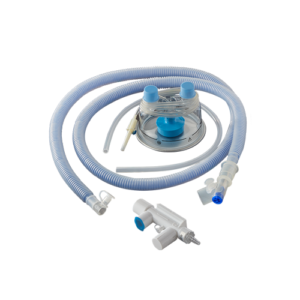

BC 630

Adult Breathing Circuit with Heated Wire for High Flow Oxygen Therapy

BC 585

Infant/Neonatal Breathing Circuit with Heated Wire for High Flow Oxygen Therapy